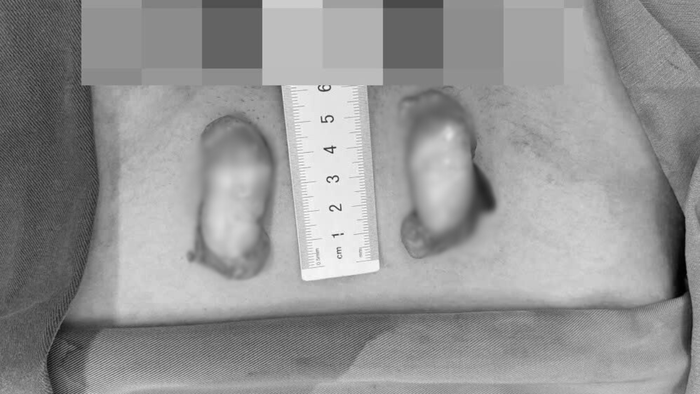

Bệnh nhân được phẫu thuật hạ tinh hoàn hai bên xuống bìu và sinh thiết mô tinh hoàn để đánh giá khả năng sinh tinh

Các bác sĩ đã tiến hành phẫu thuật hạ tinh hoàn hai bên xuống bìu và sinh thiết mô tinh hoàn để đánh giá khả năng sinh tinh. Kết quả giải phẫu bệnh cho thấy mô tinh hoàn tăng sinh xơ, ống sinh tinh teo nhỏ, không có tế bào dòng tinh - tương ứng điểm Johnson 5/10, tức quá trình sinh tinh bị ngừng hoàn toàn.